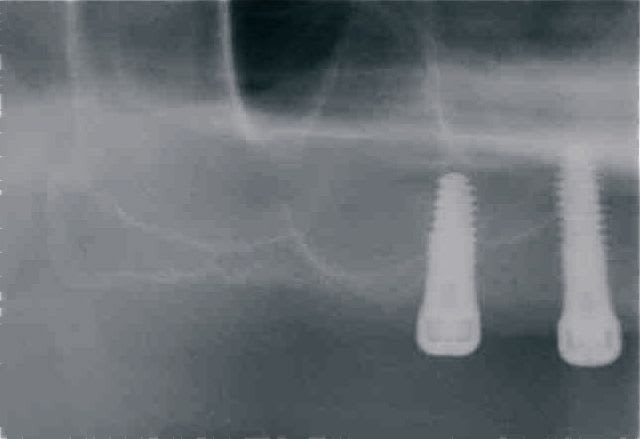

En ce qui concerne la précision, dans ce cas là et pour eviter une augmentation, j ai du placer l implant en mesio palatinal ( voir radio initiale)

En mesurant la hauteur de l os dans le septum ( dans le DVT), celui était seulement de 3 mm. Voilà pourquoi l´implant n est pas dans le septum. L´os a été condensé,la stabilité primaire a donc pu atteindre 50 Ncm.

"la meilleure des augmentations est pas d´augmentation"